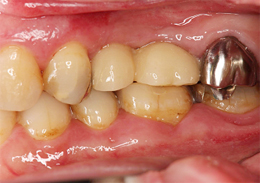

抜歯即時の上顎の「ALL-ON-4」インプラント治療、その1。